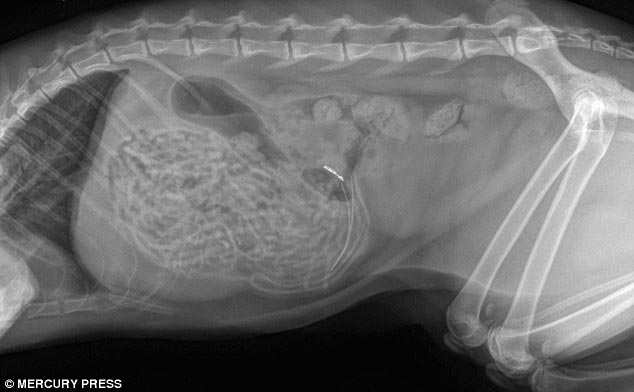

1 место - доберман Зевс, съевший 26 мячей для гольфа

![Что на ужин? Рентгеновские снимки животных, с шокирующими предметами извлеченными из их желудков предметы извлеченные из желудков животных, рентгеновские снимки животных съевших предметы, необычные предметы съели животные]()